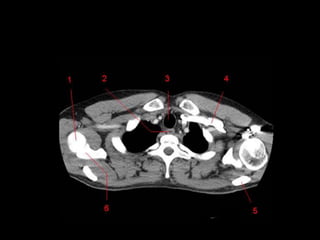

TC mediastino superior